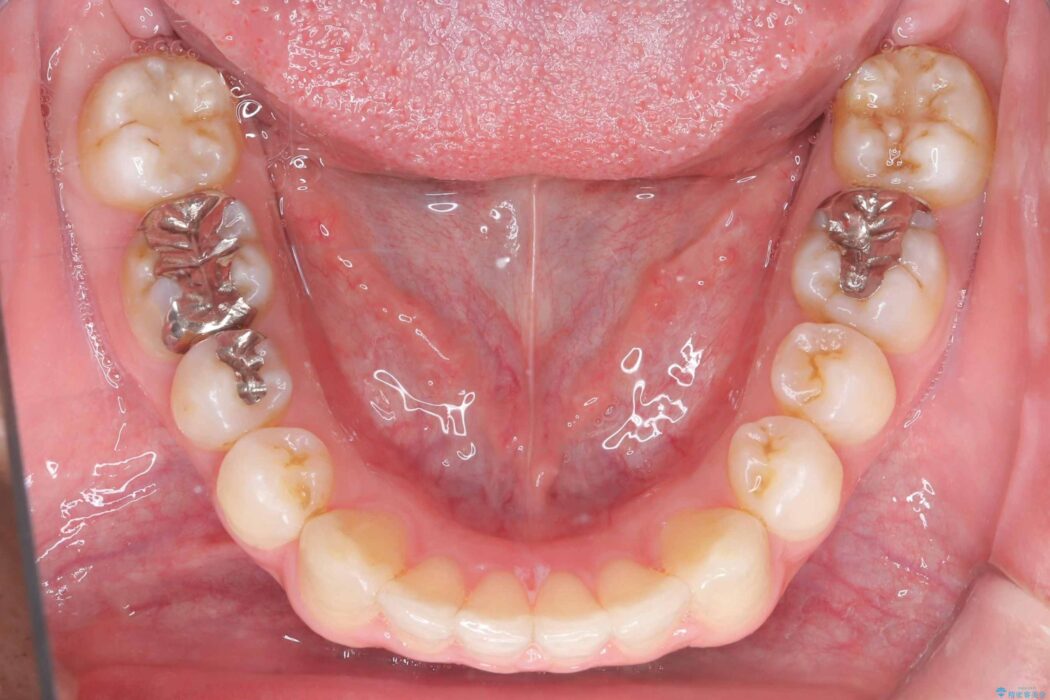

前歯の隙間とガタつきが気になるとご来院された患者様です。

正中離開・叢生のほかに、上下の奥歯が全く咬み合わないシザーズバイトの状態も認められました。